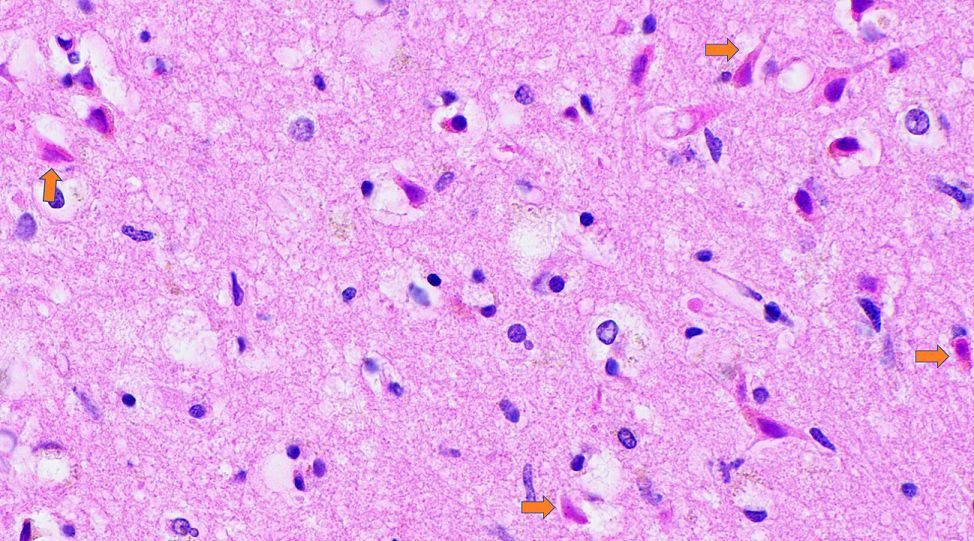

Microscopic (histologic) description

- Acute infarct (1 - 4 days) (Histopathology 2011;58:333)

- Neuronal changes: hypereosinophilic perikaryon (red dead neurons), cell body shrinkage, pyknosis (i.e., nuclear hyperchromasia), loss of demarcation of the nuclear features in later phases

- Neurons are more susceptible to ischemia than glia

- Pannecrosis: all cell populations (i.e., neurons, glia, blood vessels) are necrotic; dead cells remain visible as hypereosinophilic structures that preserve the cell and nuclear outlines (pale neurons or "ghosts")

- Neuronal changes: hypereosinophilic perikaryon (red dead neurons), cell body shrinkage, pyknosis (i.e., nuclear hyperchromasia), loss of demarcation of the nuclear features in later phases

- Subacute (5 - 14 days)

- Dense macrophage infiltration and scattered siderophages

- Variable neutrophilic infiltration

- Peripheral reactive astrocytosis and microglial activation (i.e., rod shaped microglia)

- Hypereosinophilic neurons are still present in gray matter

- Neovascularization of necrotic tissue and reactive endothelial cells

- Chronic (15 days - years)

- Cavitated lesion with vessels and macrophages surrounded by a glial scar

- Reactive astrocytes in the edge of the cavitation

- Can be piloid gliosis with Rosenthal fibers, particularly in brainstem infarcts

- Scattered hemosiderin laden macrophages typically present

- Axonal balloons can occur in all phases of ischemic injury (i.e., dilation of axons indicate injury with subsequent defective axonal transport)

- Neuronal ferrugination occurs occasionally in subacute to chronic infarcts, characterized by perykaryal mineralization (i.e., prominent basophilia)